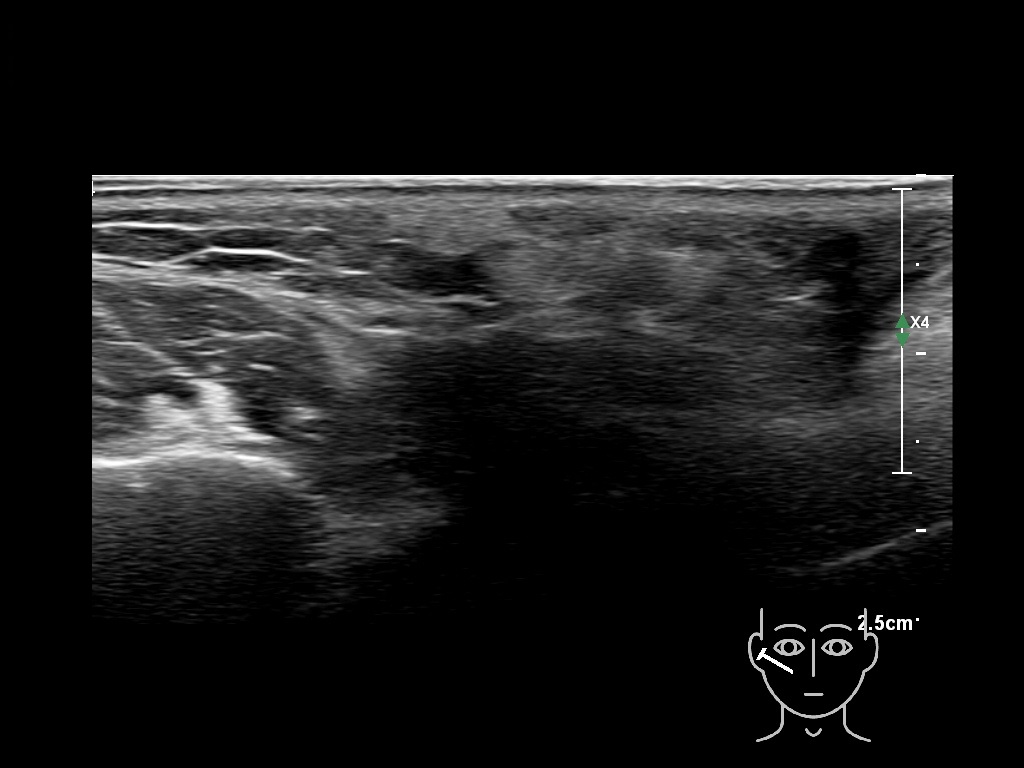

Draw in the image on the right where the fillers are located. To check if your answer is correct, please click on the secondary image.